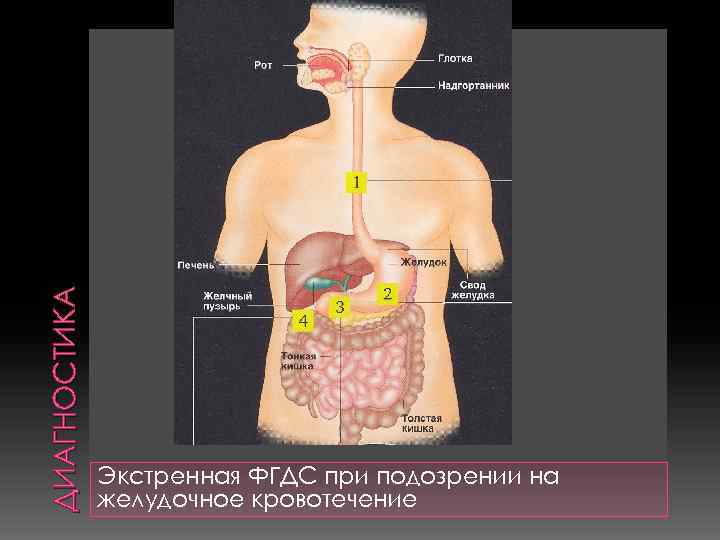

ДИАГНОСТИКА Экстренная ФГДС при подозрении на желудочное кровотечение

ДИАГНОСТИКА Экстренная ФГДС при подозрении на желудочное кровотечение